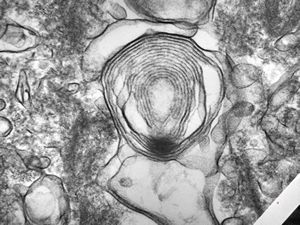

M,3m. | surfactant